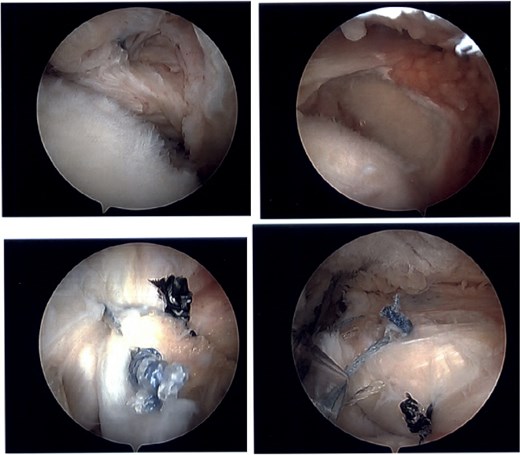

The patient was determined to be a candidate for surgical intervention given his age, ongoing symptoms, and continued dysfunction. Expectations of surgical treatment were discussed, including the possibility of a less reliable outcome regarding his right shoulder given his previous surgical history. Six weeks after injury, the patient underwent left shoulder rotator cuff arthroscopic repair. Findings included full-thickness tears of the subscapularis, supraspinatus, and infraspinatus, with glenohumeral chondromalacia (Fig. 7). He was maintained in a Frank Stubbs immobilizer for 6 weeks and then started physical therapy.

Intraoperative imaging of left shoulder arthroscopic debridement and rotator cuff repair including findings of full-thickness supraspinatus and subscapularis tendon tears, which subsequently were repaired.